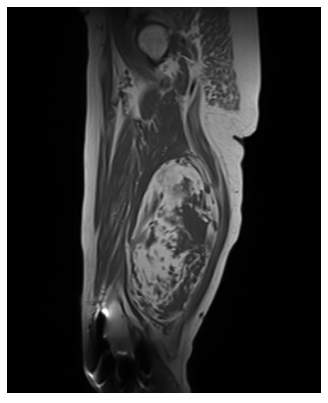

Radiographic imaging is used to help form a diagnosis. These include X-Ray, MRI, CT and Bone Scans.

An example of an MRI is shown.